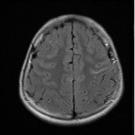

A 15-year-old Hispanic boy with no significant medical history presented to our pediatric emergency department with severe weakness. He was in his usual state of health the night prior to presentation but...